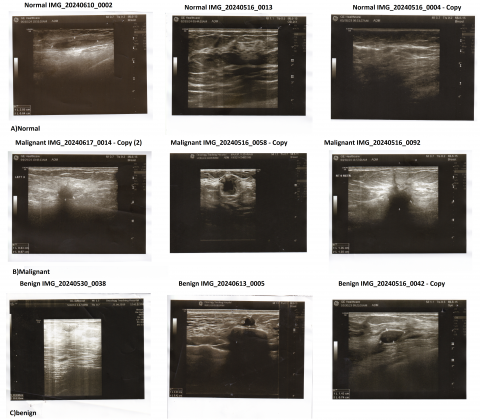

The three primary types of breast ultrasound pictures in the proposed collection dataset are benign, malignant, and normal. The dataset was sourced from an oncology teaching hospital in Iraq, and the preprocessed photos in this dataset are used to enhance machine learning and deep learning methods to detect and classify breast cancer, which consists of:

• Class malignant: 429 images

• Class benign: 289 images

• Class normal: 72 images

The dataset comprises a diverse range of ultrasound images representing various breast tissue conditions. There are three classes: (a) normal, (b) malignant, and (c) benign. This dataset is clinically valuable because it introduces normal breast tissue cases, which are not present in the Kaggle dataset, and reflects imaging variations encountered in real-world diagnostic settings.

Figure 3 shows an example ultrasound image from the normal, malignant, and benign classes. It demonstrates the complexity of visual features typically found in such cases, which are critical for classification.

Figure 3. An example from the dataset of proposed collection. the images represent a benign, malignant, and normal tumor, illustrating key diagnostic features